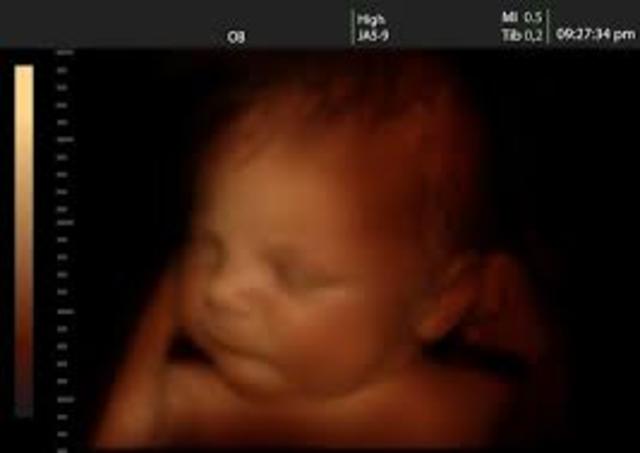

• semana 19 de embarazo

semana 19 de embarazo

A las 19 semanas de embarazo, el sistema nervioso del bebé, en especial el cerebro, se está desarrollando y creciendo rápidamente. El cartílago suave que forma el esqueleto del bebé se está endureciendo para convertirse en huesos. Por otro lado, el bebé ya hace movimientos activos que son más fáciles de sentir. Te darás cuenta de que hay momentos en los que el bebé parece estar dormido y otros en que se mueve mucho. Esto se debe a que duerme más y se despierta con más energía.